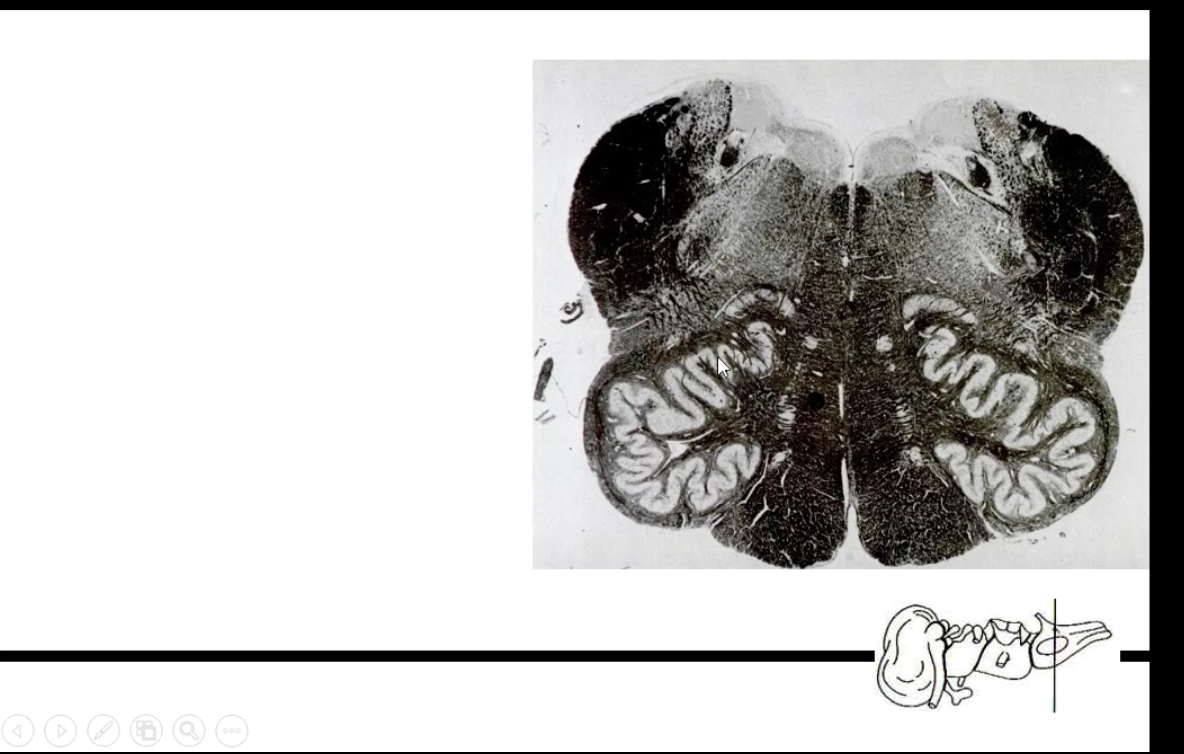

What spinal level is this?

What are some of its characteristics?